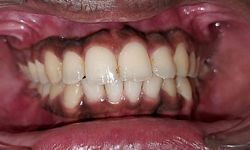

Case No: 12

Malocclusion Type: Crowding in Maxillary and Mandibular Anteriors

Mechanics: Anterior Crowding Relieved by Distalization of Mandibular Posteriors

Intra-oral : Pre-treatment : Frontal View

Intra-oral : Post-treatment : Frontal View